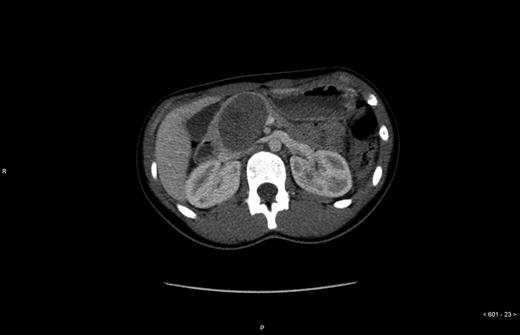

An otherwise healthy 14-year-old girl was referred to the Department of surgery Uppsala University Hospital from another hospital where she underwent a trauma-CT after receiving an elbow to the abdomen during a basketball game. The CT displayed no signs of traumatic injury, but revealed a 6.5 × 4.5 × 5.0 cm large tumor in the pancreatic head (Figs 1 and 2) which displaced the portal vein, vena cava and hepatic artery. Further investigation revealed that the patient had felt tired and had lost some weight during the past 6 months. Contrast-enhanced ultrasound with Doppler indicated a tumor with both solid and cystic structures, but no signs of vascular encapsulation. The investigation was complemented with positron emission tomography, hormone screening and an ultrasound of the heart. On the contrast-enhanced ultrasound the tumor appeared resectable; therefore no endoscopic ultrasound or biopsies were taken.

Radiologically, SPPT has known features. In CT, a well-defined heterogeneous tumor with both cystic and solid areas is observed, with the cystic areas being central and the soild areas being peripheral [8]. Calcification in the tumor has also been described [9].